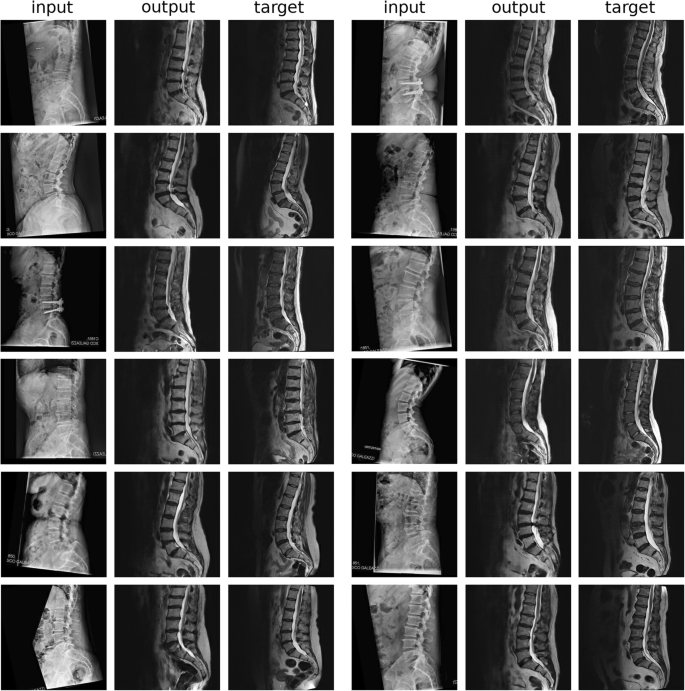

The challenging translation from sagittal x-ray projections to T2W midsagittal MRI scans provided very interesting results which included a few evident errors in the depiction of the anatomy of the patient, but on the other hand highlighted the enormous potential of generative models (Fig. 6). Indeed, the synthetic MRI images showed in numerous cases incorrect anatomies, such as unrealistically long or short vertebral bodies, especially in regions not clearly visible on the x-ray projections, such as the thoracolumbar junction. Nevertheless, the conditional GANs were able to create realistically looking MR images which include a basically correct depiction of the spinal cord, of the intervertebral discs and of the layer of adipose tissue on the back. The lower lumbar lordosis due to the different posture (standing in the sagittal x-ray examination versus supine in MRI) was also realistically captured.

Representative results (12 patients) of the translation from sagittal x-ray projections to T2W midsagittal MRI scans. input: original x-ray image, registered to match the alignment of the original MRI; output: synthetic T2W midsagittal MRI; target: original T2W midsagittal MRI. A few gross errors in the anatomy can be identified: the L1 in the first and fourth patients on the left; the sacrum in the first patient on the right; the thoracolumbar junction in the third patient on the right; L1 and the sacrum in the fourth patient on the right